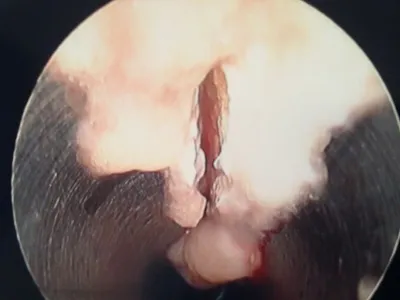

Pictures during an endoscopic plantar fasciotomy or release. The medial band of the fascia is visualized on the left. The two right pics are during the release of the band.

Intraop Pics of EPF